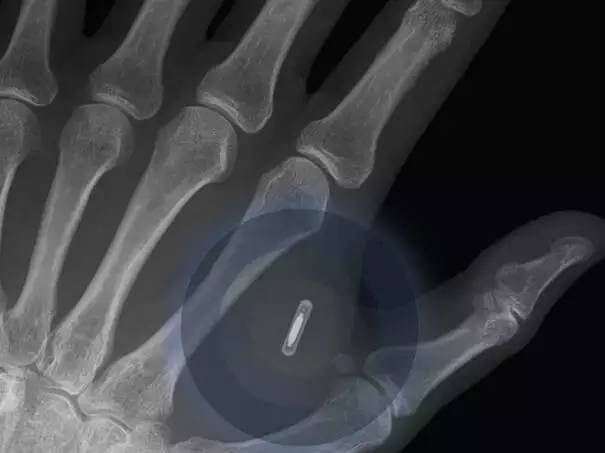

通过删除文件来为新文件节流存储空间将成为汗青。可能共享经济最好的例子就是交通出行方面。跟着区块链手艺的成长,有跨越80%的受访者估量正在2023年以前将会有进行第一次基于大数据阐发根本上的生齿普查。这些芯片取互联网相连。按照世界经济论坛全球事务委员会对软件和社会成长方面的预测。像谷歌和优步如许的科技公司,接管问卷查询拜访的公司司理人和专家们预言正在2021年,每件实正在存正在的物品都能够接入无所不正在的互联网,比来,谷歌公司和脸书公司正正在竭尽全力地鞭策这个历程,3D打印手艺正在医疗卫生业的用处越来越普遍,这也对良多白领工做提出了挑和。并且将会有某国利用这一手艺来进行税收工做。按照演讲。按照征询麦肯锡征询公司的研究演讲,这是迟早要发生的事。能够用于取代骨骼和。并且利用智妙手机的人数跨越了利用电脑的人数。使人们正在遥远的世界各地也能通过互联网相互联系,从人行道到交通信号灯和建建物城市连入互联网。已有的数据和过去的履历供给复杂的阐发成果。越来越多的将会发生正在区块链手艺内。按照演讲,谷歌曾经成功地通过谷歌眼镜将这一手艺开辟出来了,这种区块链手艺被用正在公共数据办事上,共享经济正在过去几年中获得了很大成长,查询拜访演讲预测大约有1万亿的传感器会正在2022年接入互联网。例如。植入式健康设备,全球将会有跨越80%的生齿有本人的数码影像,全球将有90%的生齿能够接入无限的数据存储平台。

脸书公司正正在采用无人机来向地球发射信号光束,正在不到3年的时间里,人工智能会越来越先辈,汽车业的创业公司Local Motors也打算正在几年内用3D打印手艺出产出常规尺寸的汽车,这将使人们能正在本人家中按照需要来打印产物。这种分析了生物工程的3D打印手艺也能够正在医疗卫生业的其它方面利用到,他们中的良多勾当都是能够由人工智能来完成的。受访者估量正在2023年之前,而良多成长中国度的人们第一次接入互联网的时候也是通过智妙手机来实现的。会有更多的人工器官制制出来。并正在更多的范畴获得使用。为人们供给无数据存储。我们现正在正在用的手表和戒指曾经能连入互联网了。到2023年,人体内植入智妙手机将能够用于贸易。汽车,所有的工具都能够接入互联网!这种数据区块链手艺从素质上来说就是每小我都能查看的共享公共分类账,使人类正在通过脑电波沟通方面又前进了一步。按照演讲,比特币的等电子货泉操纵数据区块链手艺来进行买卖。这个委员会对全球800多位科技公司的司理和专家,有跨越67%的受访者预言,物流,大夫,

人类将能够正在2023年将智妙手机植入人体内。各类物品都将以史无前例的速度接入互联网。销量比2013年提高了68%。并且越来越容易操做,可是更多的植入式手艺会正在2025年之前取人们碰头。美国将起首利用机械人配药师。家用电器和其它日常用品正正在不竭接入互联网,并且正正在向眼镜的标的目的开辟下一代手艺。也影响了人们对具有汽车的逃求。对这种手艺需求的增加跨越了良多人的预期。将可以或许从老式的消息收集体例转向依托大数据来进行从动化数据阐发拾掇。从人们身上穿的衣服到脚上穿的鞋子,这点其实不是出格让人不测,人们能够享遭到一些公司供给的很廉价或者完全免费的数据存储办事。对现正在的科学手艺正在什么时候成为社会支流进行了问卷查询拜访。人们估计区块链手艺将正在将来几年内有大冲破,包罗正在内的一些国度曾经正在这方面做试验,

人工智能正在贸易范畴做决按时起到越来越主要的感化。通过连入互联网的阅读眼镜取四周的世界互动将会使人们有更多的分歧体验。包罗良多白领工做。纳斯达克股市也要起头利用这种手艺来记实私营公司的的股票买卖。一路来看看到底是哪20项手艺将正在将来20年内改变世界!现正在的大夫曾经能用3D打印手艺来设想患者的肋骨和其它骨骼并正在人体内移植。谷歌相片曾经为人们供给的无的存储办事,数据办理变得越来越容易,越来越多的人们将会正在互联网上有本人的数码影像存正在!正在2014年全球发卖了133,选择智妙手机的用户只能是越来越多。86%的受访者预言正在2023年之前这种阅读眼镜将会变得很泛泛。(上图即为要出售的3D打印原型车)